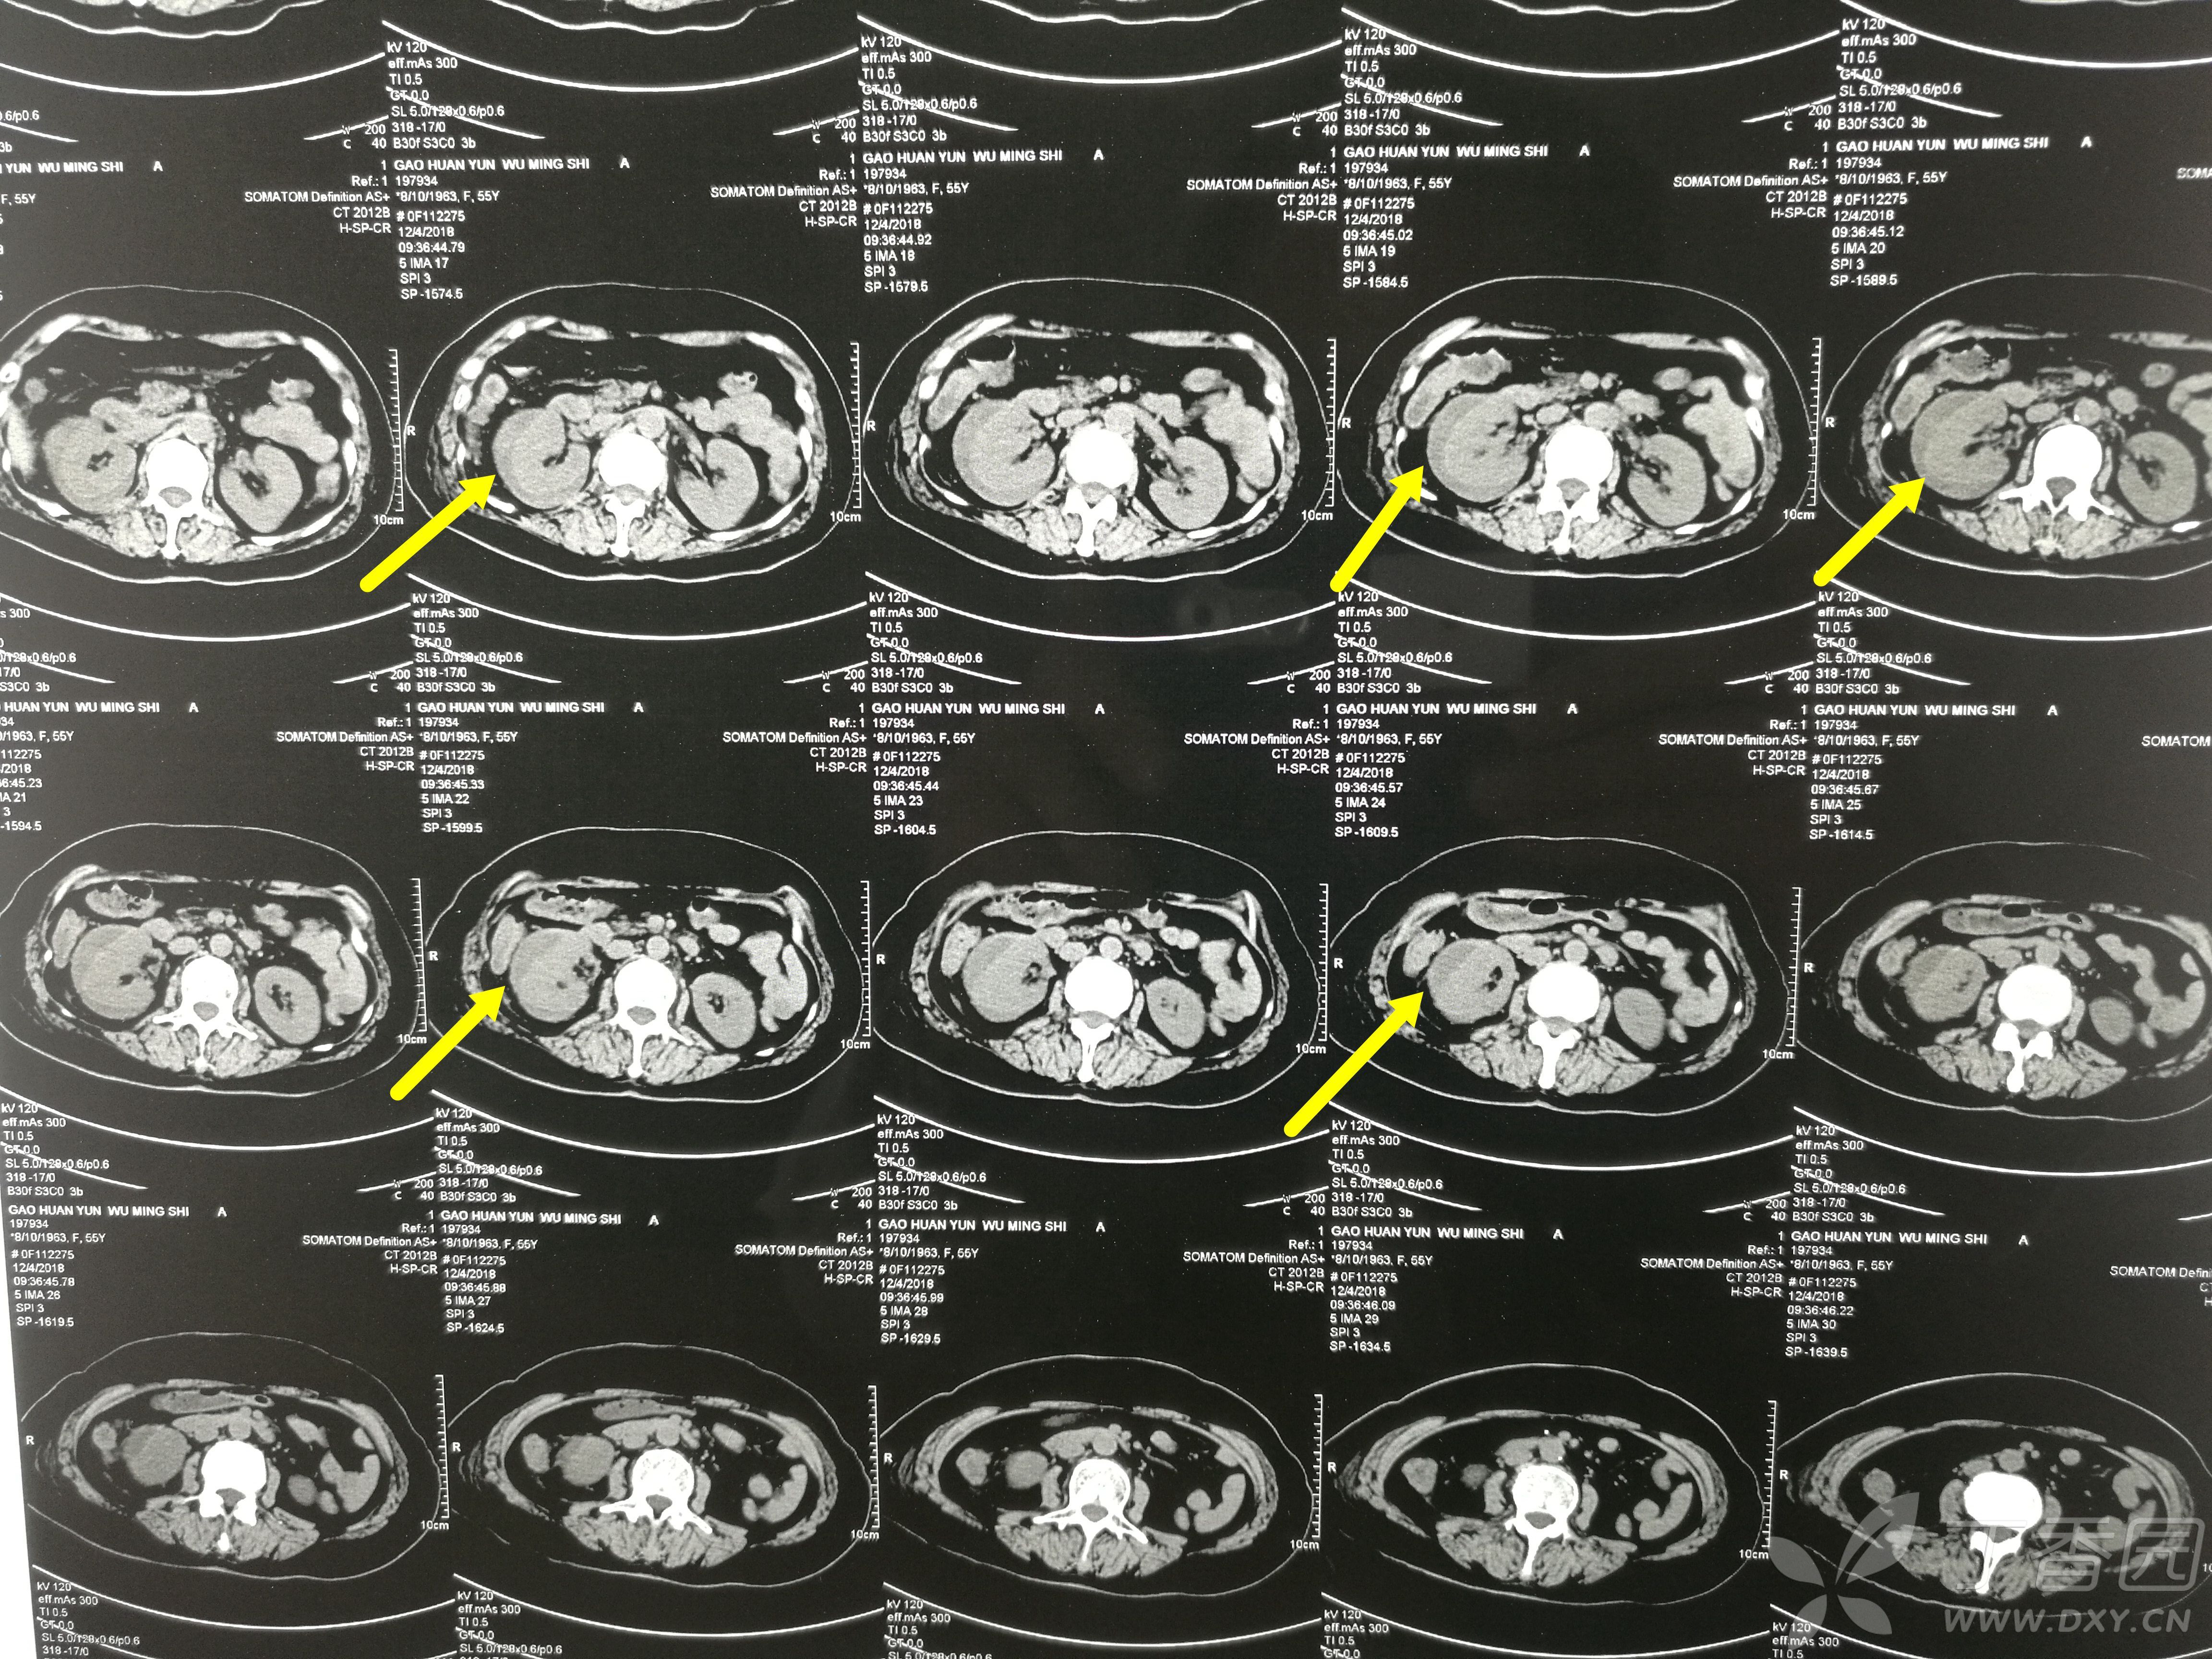

【病例】肾挫裂伤伴包膜下血肿1例ct影像表现

无血尿,入院查ct提示:黄箭头所指为右肾包膜下高密度影,考虑血肿;绿